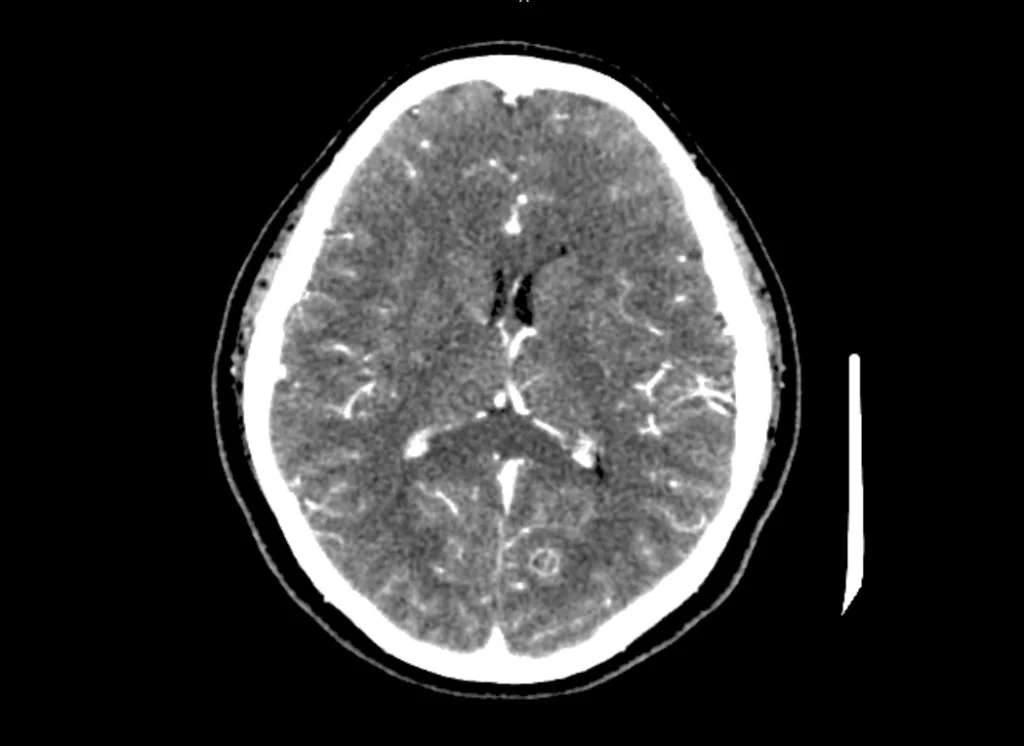

Na tomografia de crânio com uso de contraste, são analisadas as estruturas vasculares da região estudada. A solução de contraste iodado é administrada por via endovenosa e distribui o contraste entre as estruturas com fluxos sanguíneos, realçando as estruturas hipervascularizadas, mostrando, por exemplo, tumores ou processos inflamatórios.

Este exame, em sua grande maioria, é realizado sem o uso de contraste, caso o uso seja necessário, deve ser prescrito atentamente pelo médico solicitante ou médico radiologista.